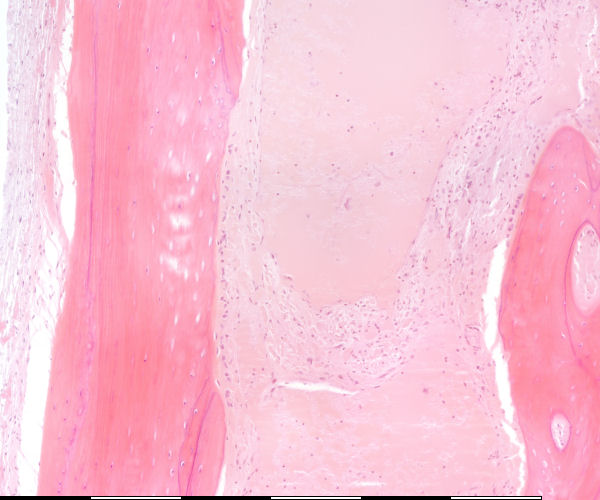

Medium magnification of immature bone

Osteosiete / Osteocytes Lakunae / Lacunae Groeilyne / Growth reversal lines Aktiewe periosteum / Active periosteum Losmasige bindweefsel / Loose connective tissue Osteoblaste / Osteoblasts Laag van osteoblaste / Layer of osteoblasts Lamellêre laag kortikale been / Lamellar layer of cortical bone